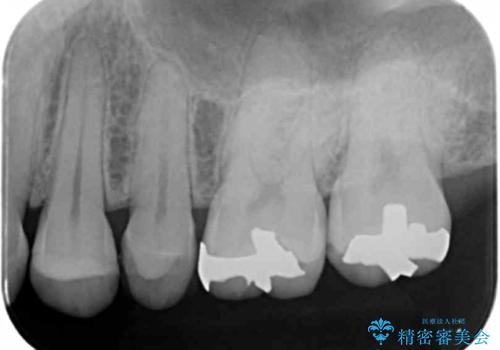

- 銀歯のやり替えをご希望で来院されました。

虫歯を取りつつ銀歯を外し、セラミックインレーでの修復処置を行います。

- 左上567 セラミックインレー:77,000円×3本費用は治療当時の料金となります

処置中に手前の歯の詰め物の不適合が確認されたため、追加で治療していくこととなりました。

銀の詰め物と不適合な詰め物を精度の良いセラミックインレーに変えることができました。